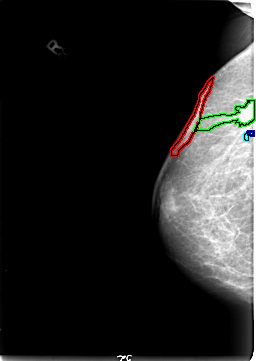

FILE: B_3025_1.RIGHT_MLO.OVERLAY

TOTAL_ABNORMALITIES 4

ABNORMALITY 1

LESION_TYPE MASS SHAPE IRREGULAR-ARCHITECTURAL_DISTORTION MARGINS ILL_DEFINED-SPICULATED

ASSESSMENT 5

SUBTLETY 5

PATHOLOGY MALIGNANT

ABNORMALITY 2

LESION_TYPE CALCIFICATION TYPE PLEOMORPHIC-FINE_LINEAR_BRANCHING DISTRIBUTION SEGMENTAL

ABNORMALITY 3

ABNORMALITY 4